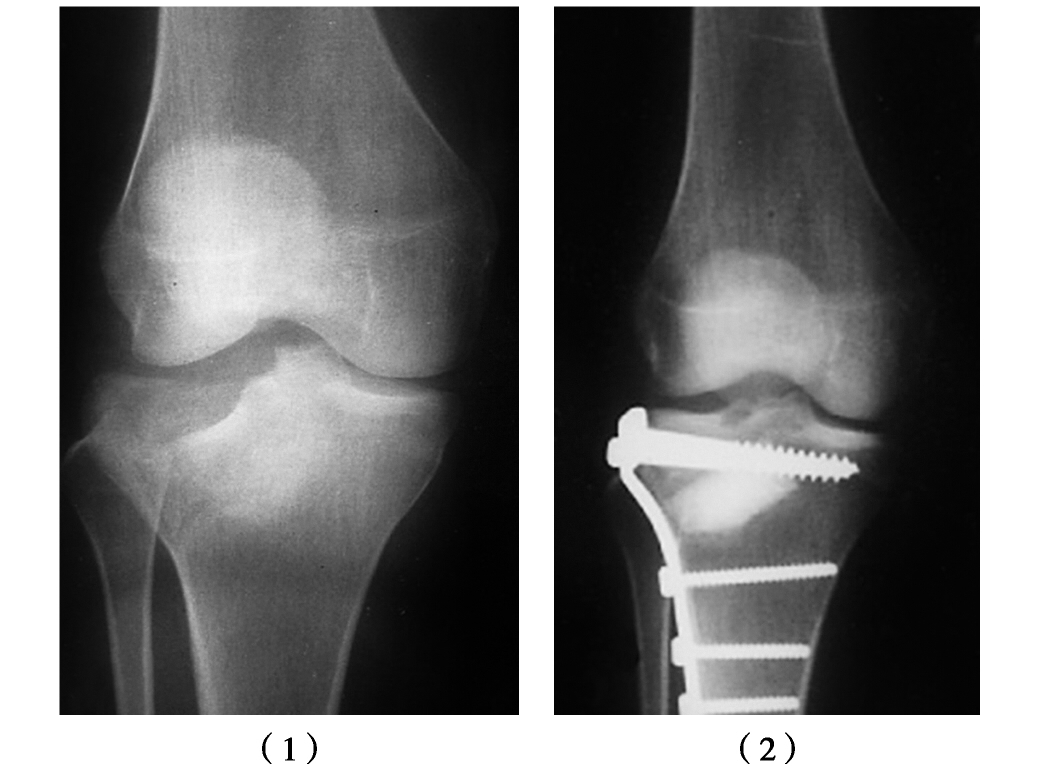

生物活性陶瓷虽具有良好的生物相容性、化学稳定性及通过离子交换等形式与骨组织发生强有力的化学性结合,但此类材料的最大缺陷是脆性大、抗弯强度低,易于折裂,而且不易吸收。一般仅用于修复需较小负荷的骨缺损,如胫骨平台骨折术后预防关节面塌陷的支撑植骨(图4-0-7),或肿瘤切除后空腔的填充。

图4-0-7 胫骨平台骨折手术前后X线片

(1)术前下陷的胫骨平台;(2)复位内固定及羟基磷灰石关节面下支撑